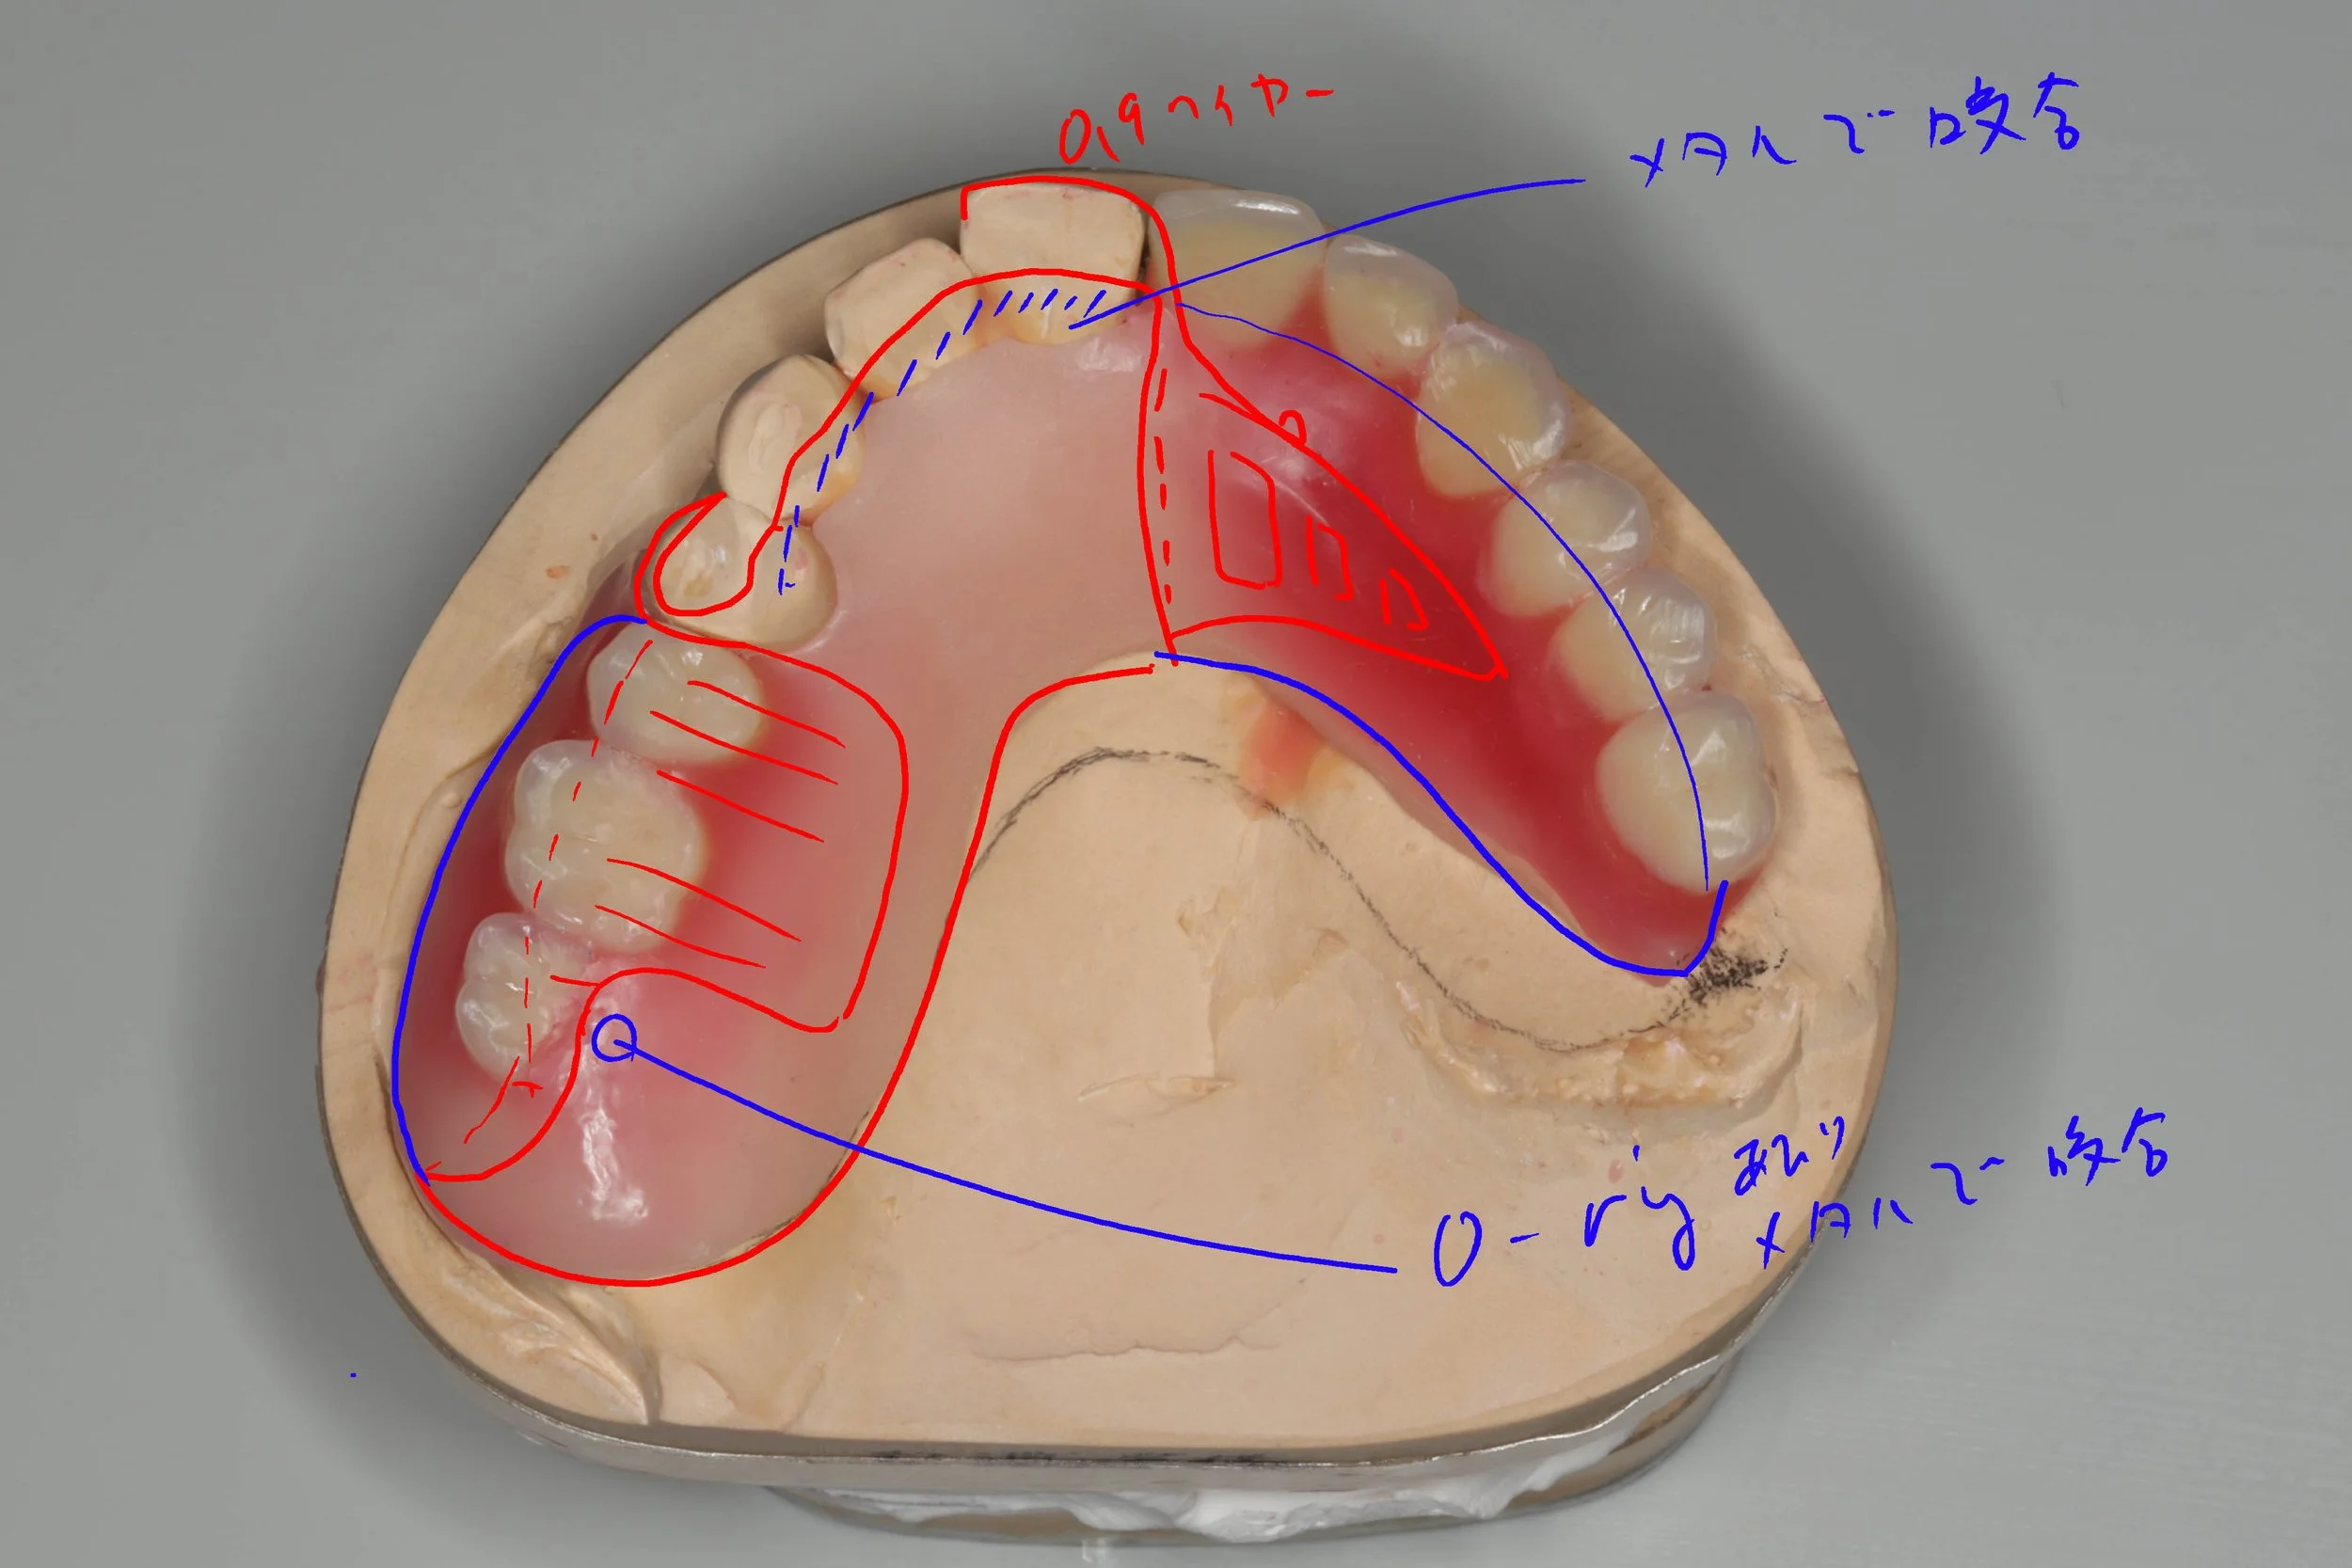

デジタルデンチャー

奥の歯には、金属で入れ歯を止めるバネを製作し、前歯の見える部分には、透明なレジンクラスプを使用しました。